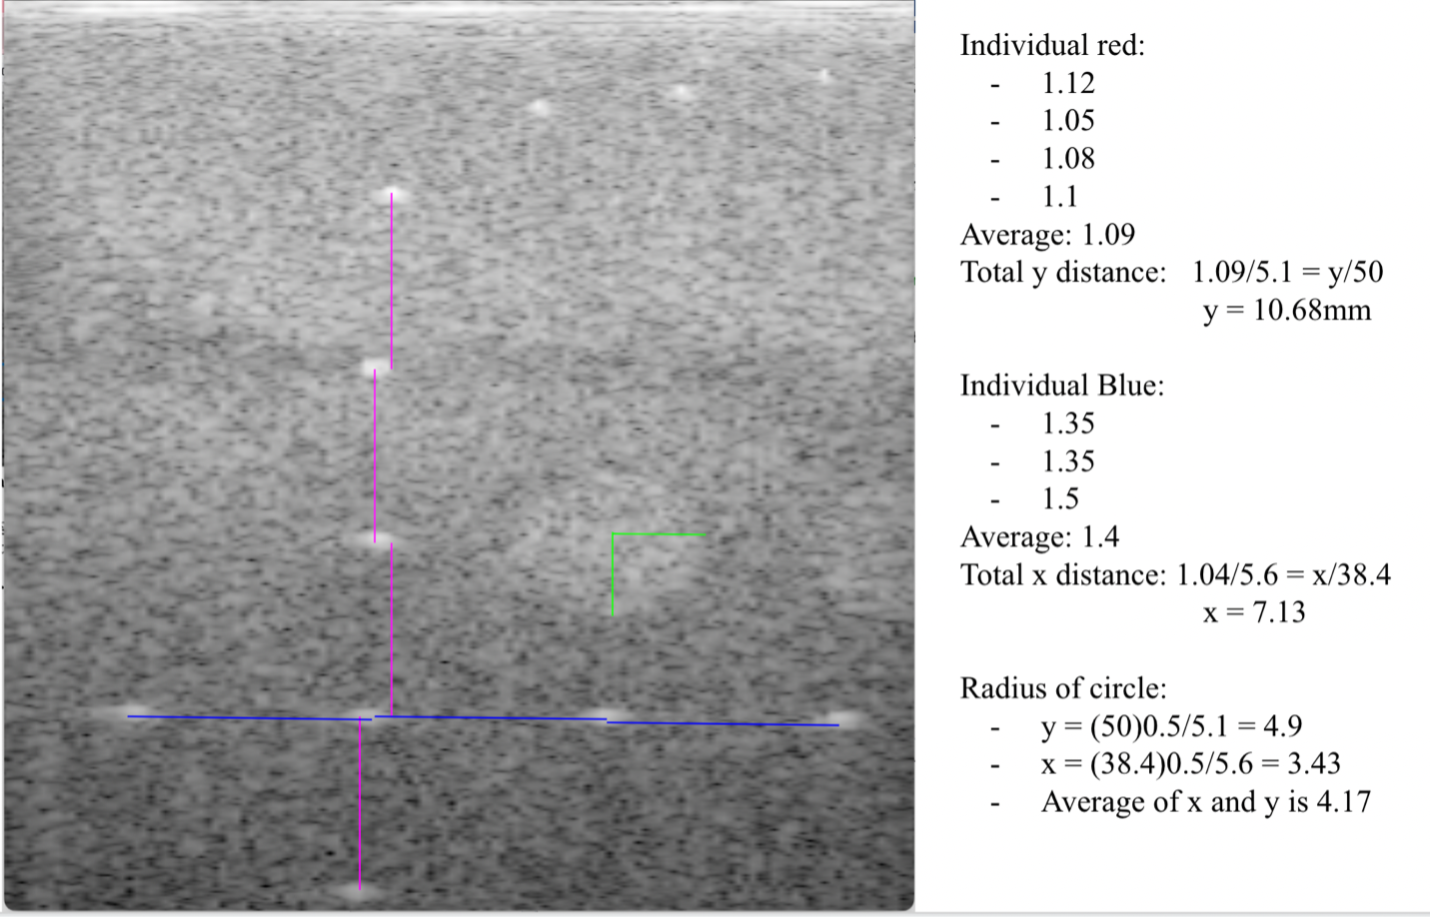

The image was analyzed and used to measure the distance between points of interest.